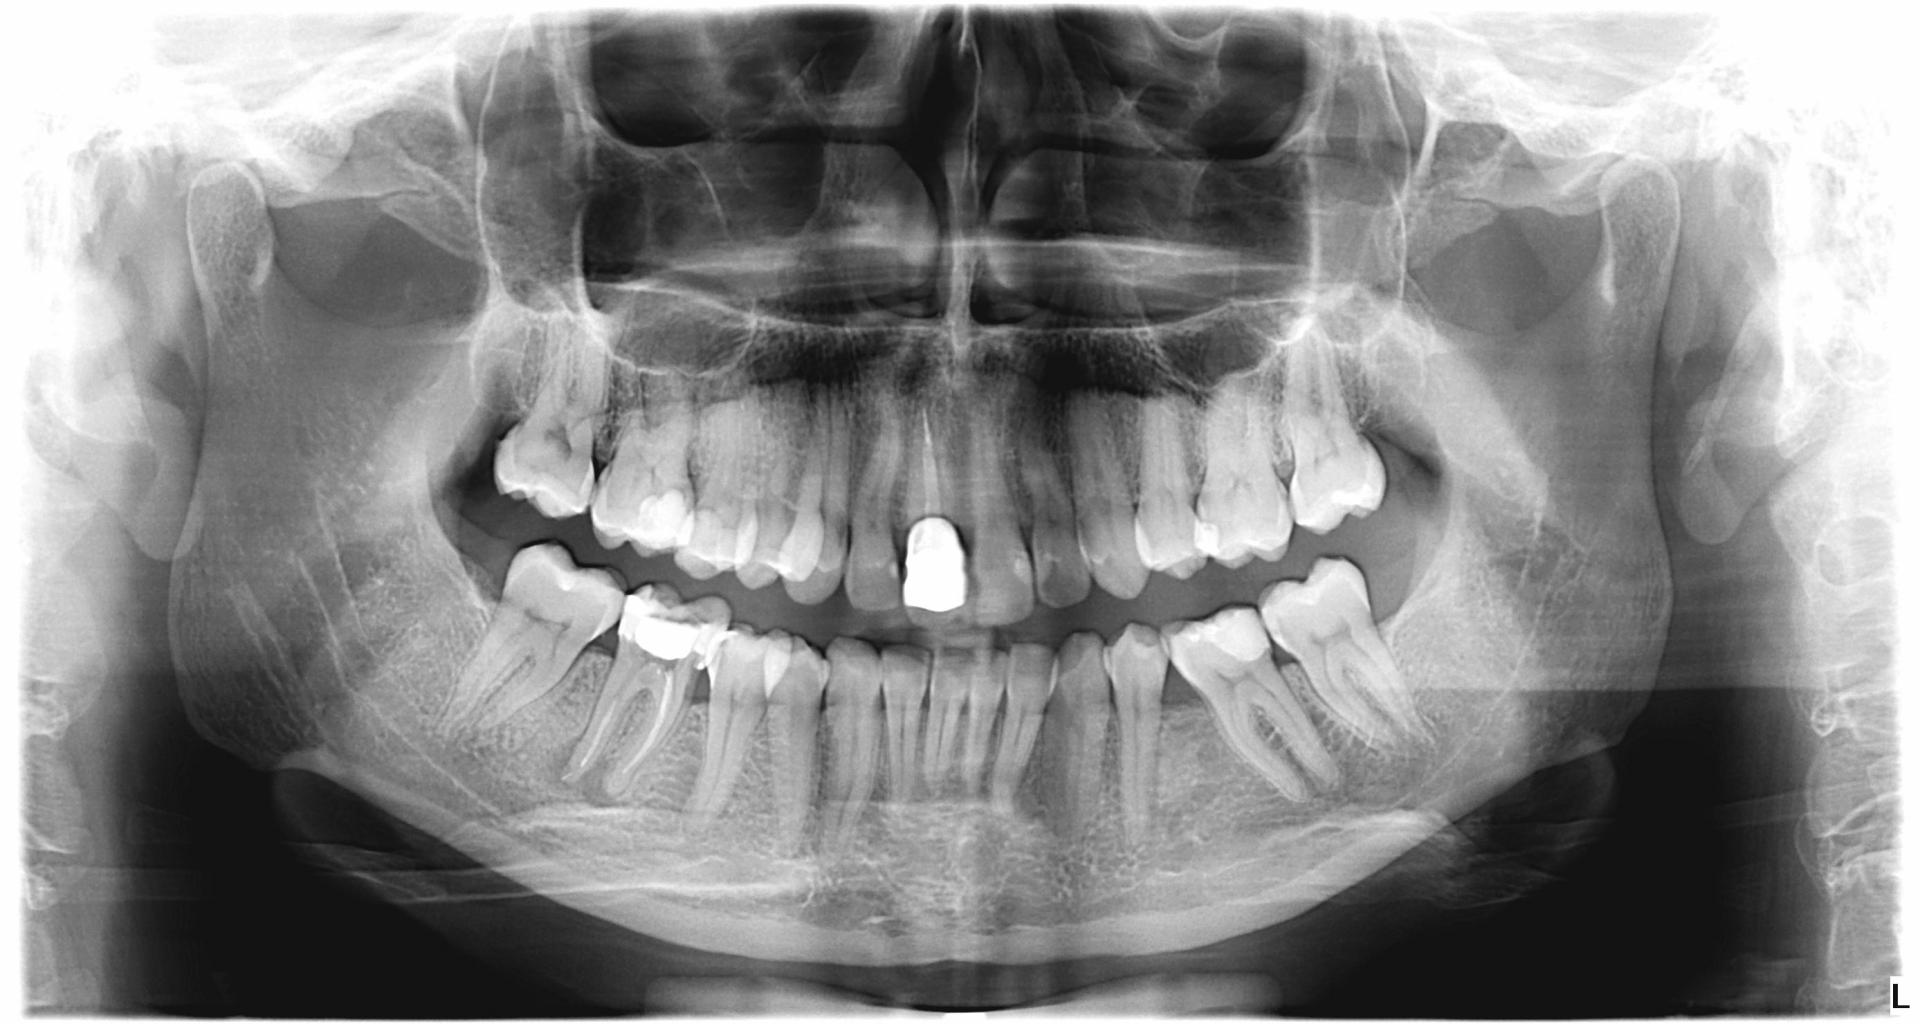

- Panoramic photo